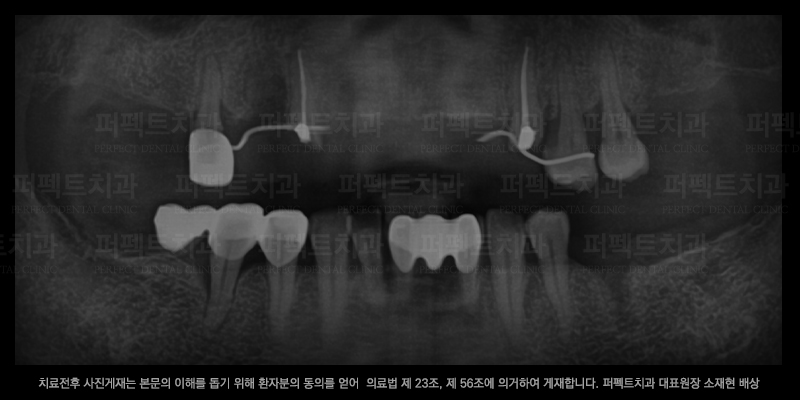

임플란트 전/후 사진 비교

임플란트 수술 전

위 사진은 실제 선릉역치과에서 임플란트 치료를 받으신 환자분의 치료 전/후 사진입니다.

임플란트는 다른 치과치료들 보다 더 신중해야 하는 치료이기 때문에

풍부한 경험과 실력이있는 원장님한테 치료를 받으셔야 합니다.